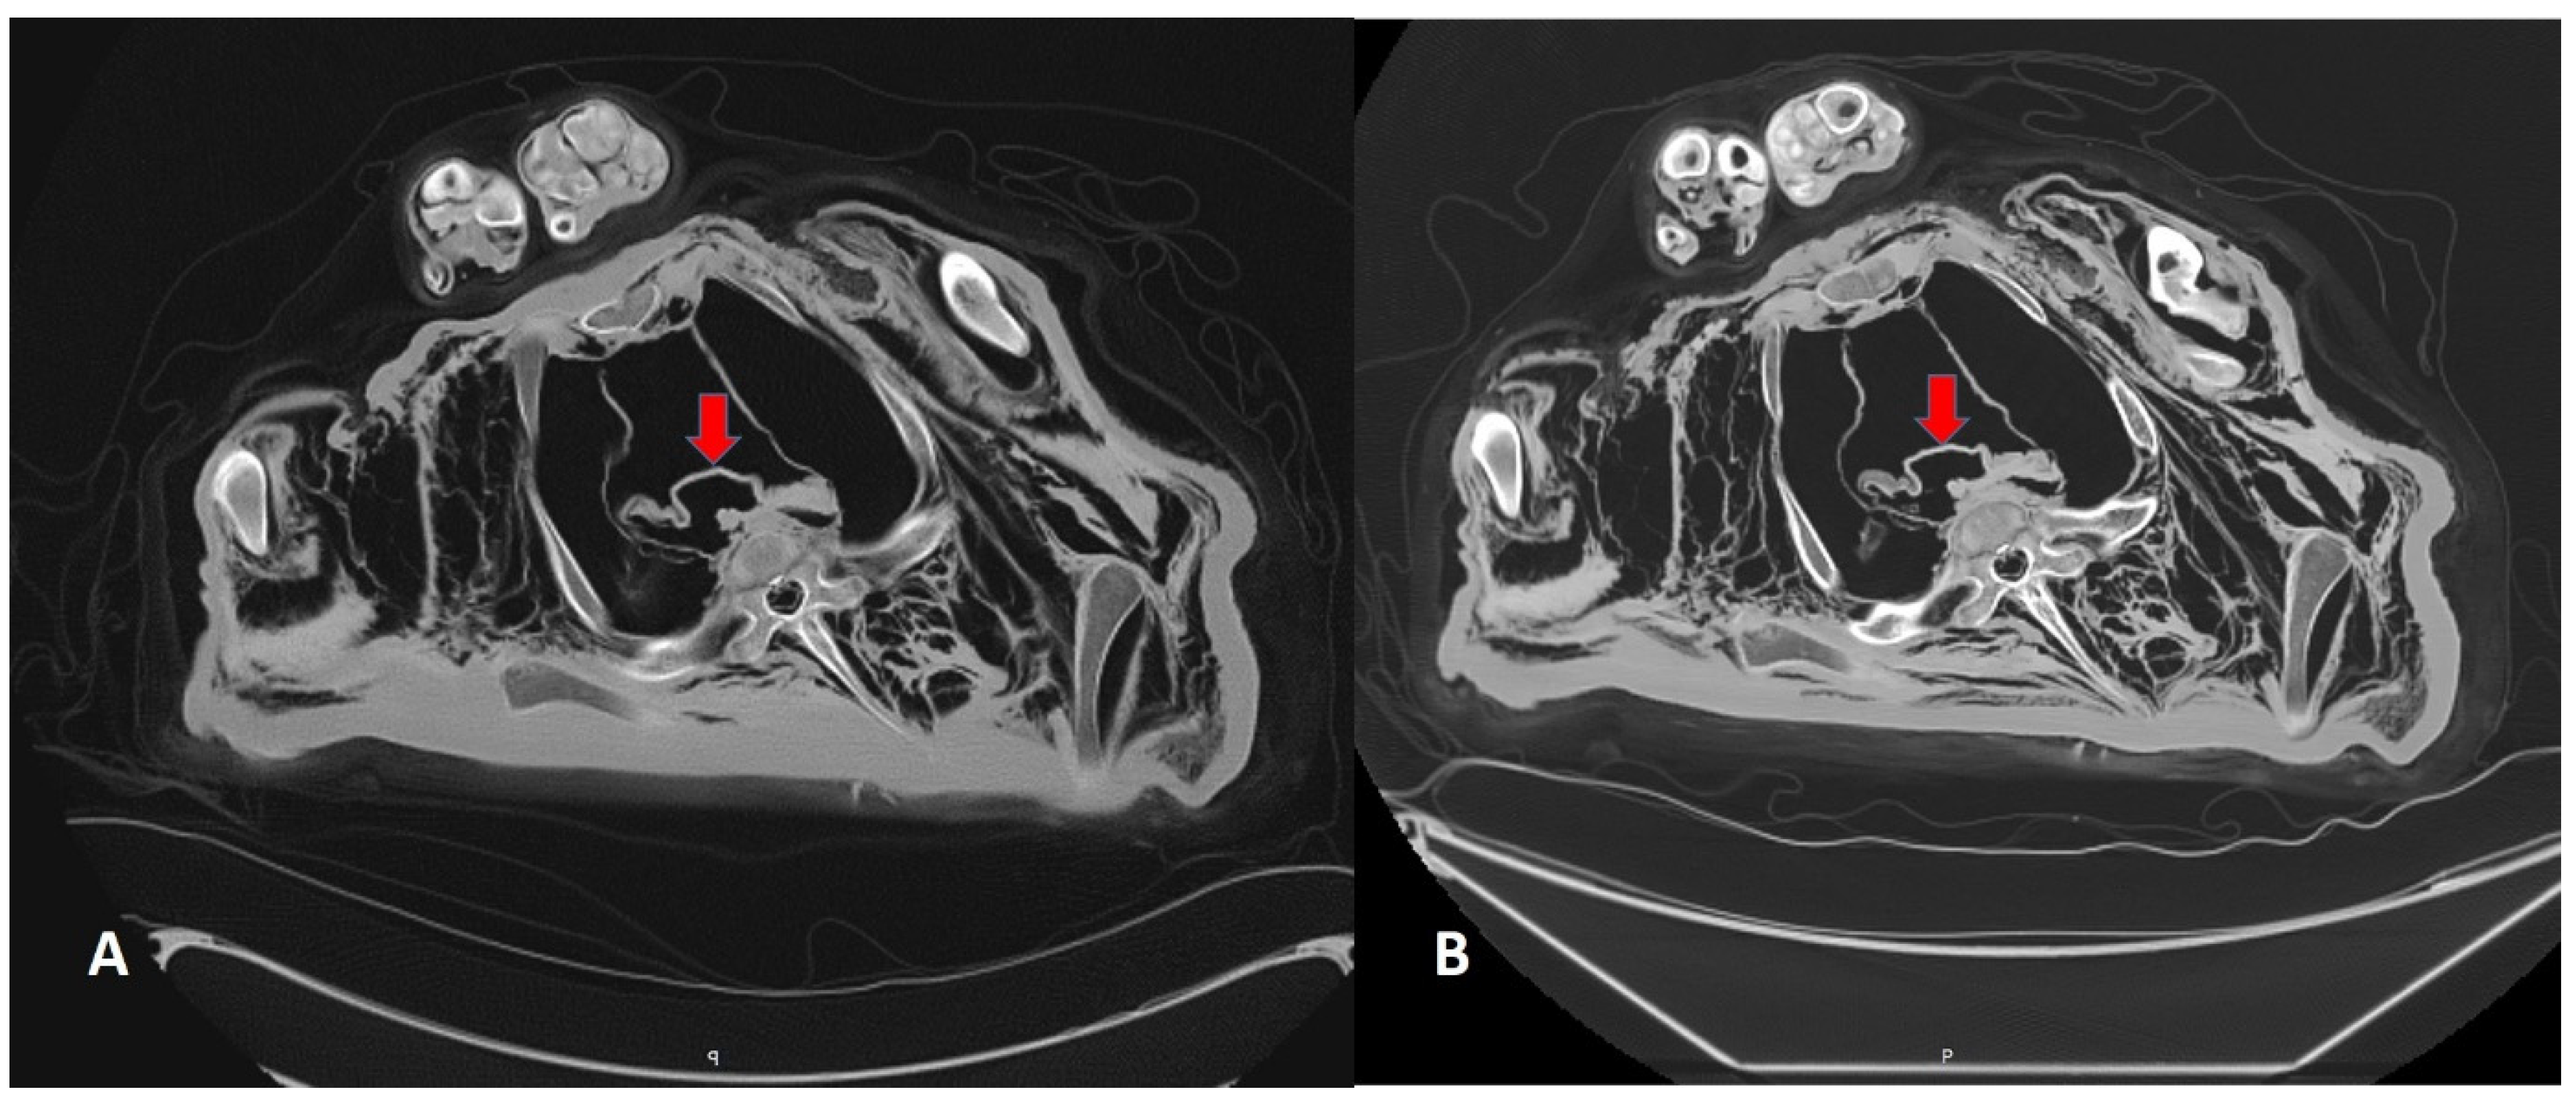

3.2. CT Scans After 7 and 13 Years